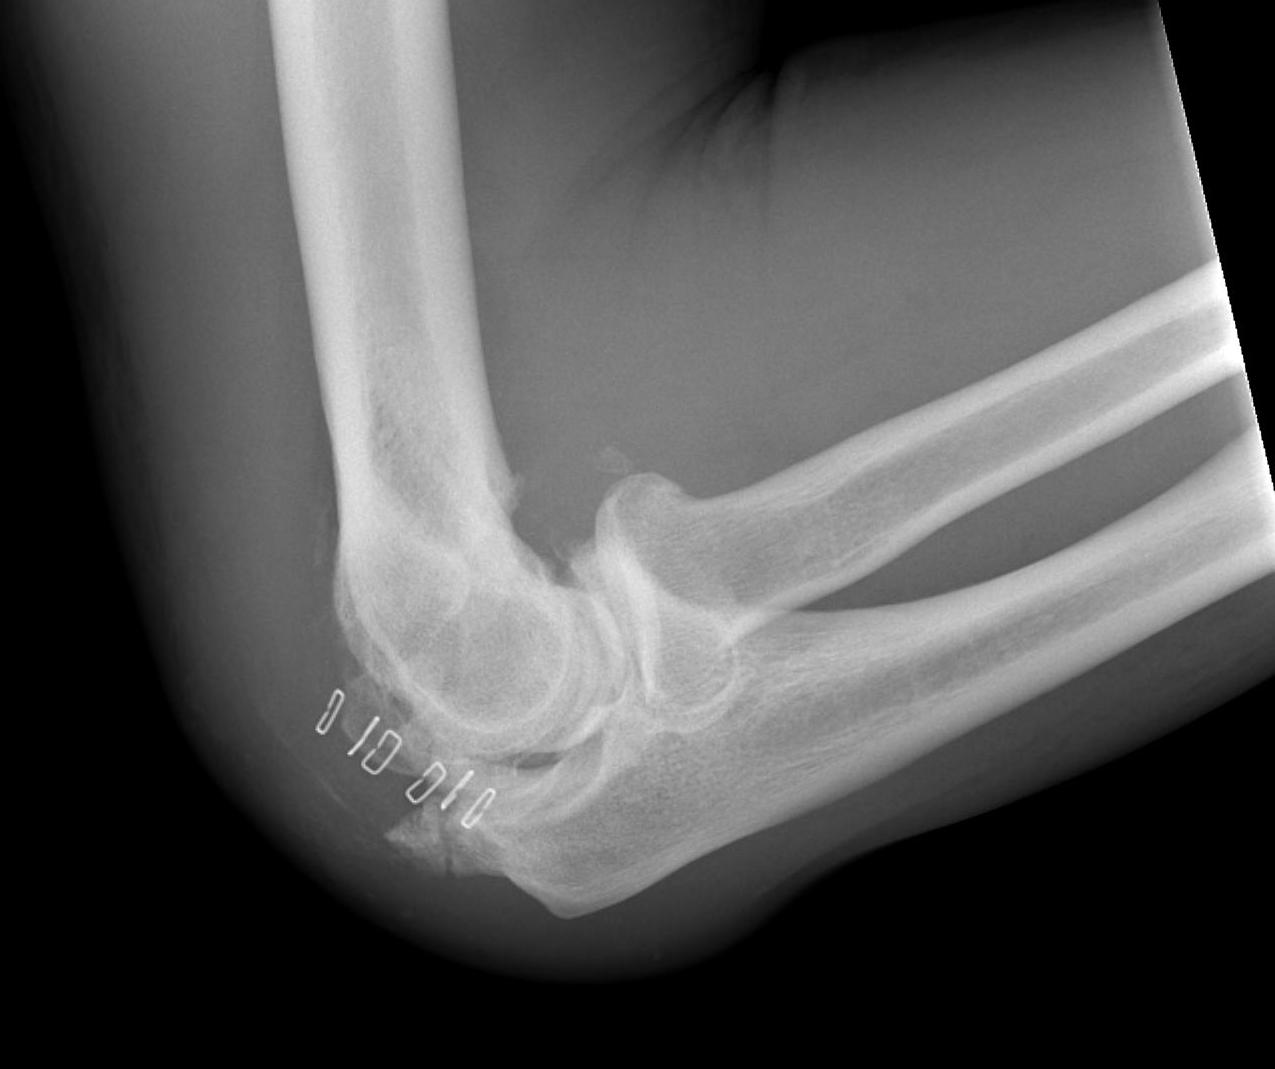

Trauma

- elbow fracture / dislocation

X-ray

Changes occur 2-4 / 52 after injury

Initial cotton candy appearance

- then osseous in appearance

- not attached to bone

- can be resorbed

Mature bone peripherally